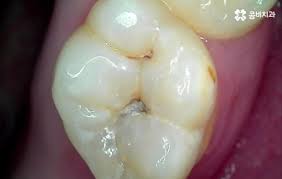

- 심한 충치: 충치가 깊어져 신경까지 도달한 경우

- 자발통 & 야간통: 별 자극 없이 욱신거리거나 밤에 통증